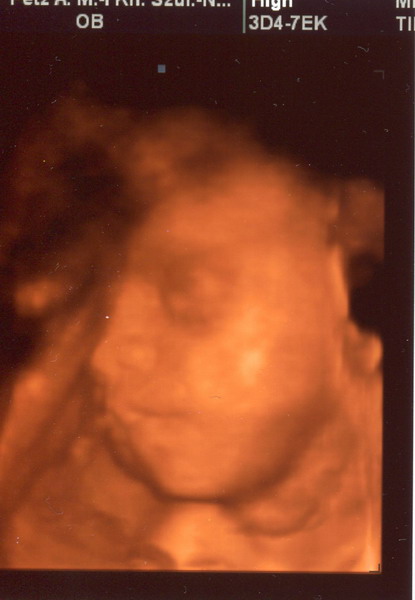

Gergő:

Kép

Majdnem egyforma a két kép amit kaptunk, de azért remélem nem baj, hogy mindegyiket megmutatom. :D

Na, szóval minden a helyén van, csuda édes pofa volt Gergő. Már 1160 g körül van a súlya, ami miatt azt mondták, hogy valószínűleg idősebb a megállapított kornál. (vagy ő is jó nagy lesz... :shock: ) De szerintem is idősebb lehet, hisz ezt támasztja alá az is, hogy a ciklusom 26. napján pozi lett a 25-ös erősségű terhességi tesz, meg a 12. heti uh szerint is nagyobb volt kb 4 nappal a kiírtnál.

Amúgy az elején még mutatta a kis pofiját, de aztán egy idő után hátat fordított... De szerencsére láttuk ahogy nyitogatta a szemét, játszott a lábujjaival, a kezét a szájába vette, számlálgatta az ujjacskáit és mozgatta a kis száját. :D amikor hátat fordított, az is látszott, hogy a tarkóján van haja! :D Bencének is pont ott volt sok haja amikor megszületett, a feje tetején kevés volt neki, de ott lent elég sok. Úgyhogy ebben legalább is hasonlít bátyusra!

Jaj Lányok, én annyira boldog vagyok!!!!!!!!!!!!!!!!!!!!!!!!!!!!!!!!!!!!